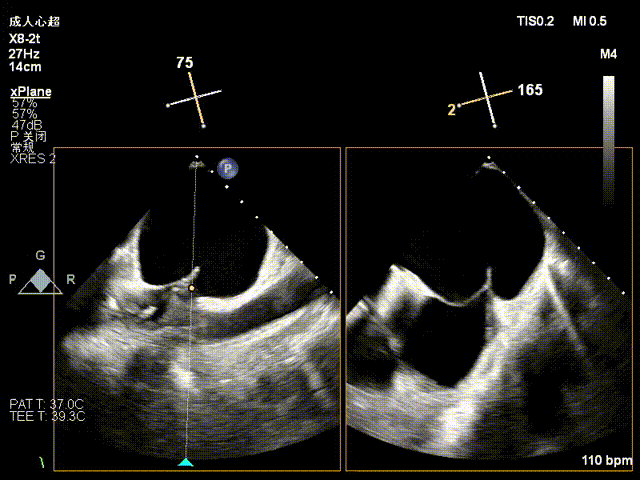

术前X-plane

术前X-plane上彩

2、后叶室性栓系,质地菲薄,瓣叶精准捕获的难度增大;

3、房间隔存在膨出瘤,房间隔穿刺的难度增大。